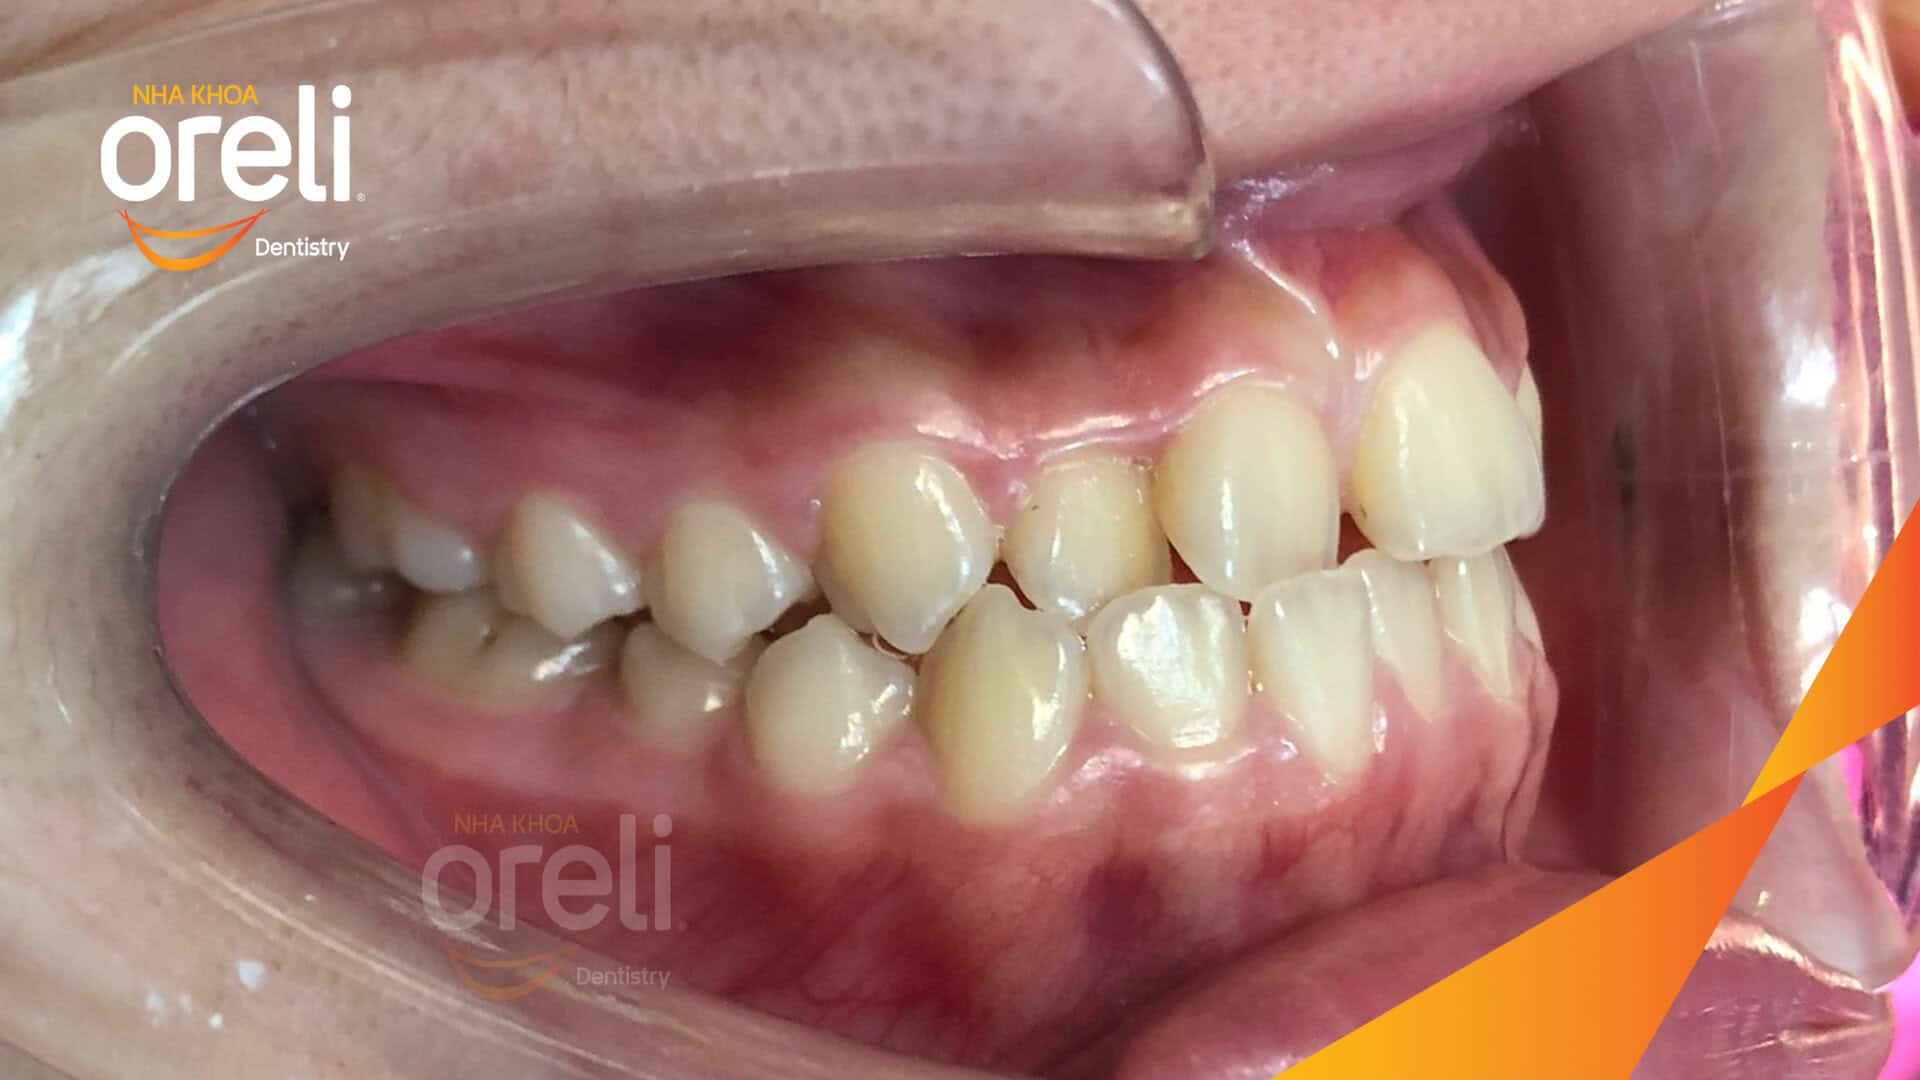

Ca niềng chỉnh chen chúc sai khớp cắn hạng 3 móm nhẹ – Kết quả thực tế ở Oreli Niềng răngChen chúcMóm Xem thêm